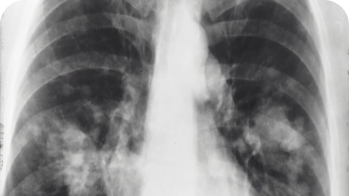

РЕНТГЕН

Рентгенографические исследования.

от

1200 руб